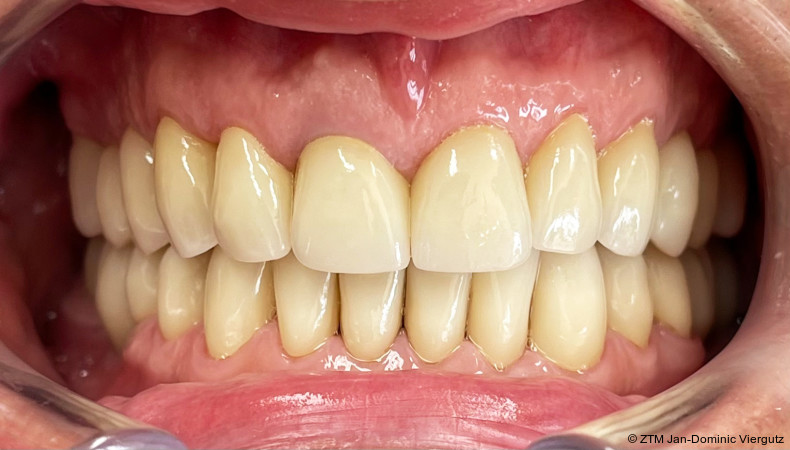

Der Einsetzprozess der Kronen wurde erneut unter Narkose durchgeführt, um dem Patienten maximalen Komfort und Sicherheit zu bieten. Zunächst erfolgte die adhäsive Befestigung (Multilink Automix, Ivoclar) der Kronen auf den natürlichen Zähnen, wodurch eine stabile und dauerhafte Verbindung geschaffen wurde. Anschließend wurden die Implantatkronen (Prettau 3 Dispersive, Zirkonzahn) mit dem empfohlenen Drehmoment verschraubt.

Die konsequente Anwendung der Michigan-Schiene führte zu einer vollständigen Beseitigung der Kiefergelenkschmerzen und ermöglichte eine nachhaltige Entlastung der Kiefergelenke. Die monolithische Gestaltung der Seitenzahnkronen erwies sich als besonders effizient, da sie eine präzise, zeitsparende und stabile Versorgung erlaubte. Auch in der Nachsorge zeigte sich der Patient dauerhaft beschwerdefrei und äußerte sich durchweg zufrieden mit dem funktionellen und ästhetischen Ergebnis der Behandlung.